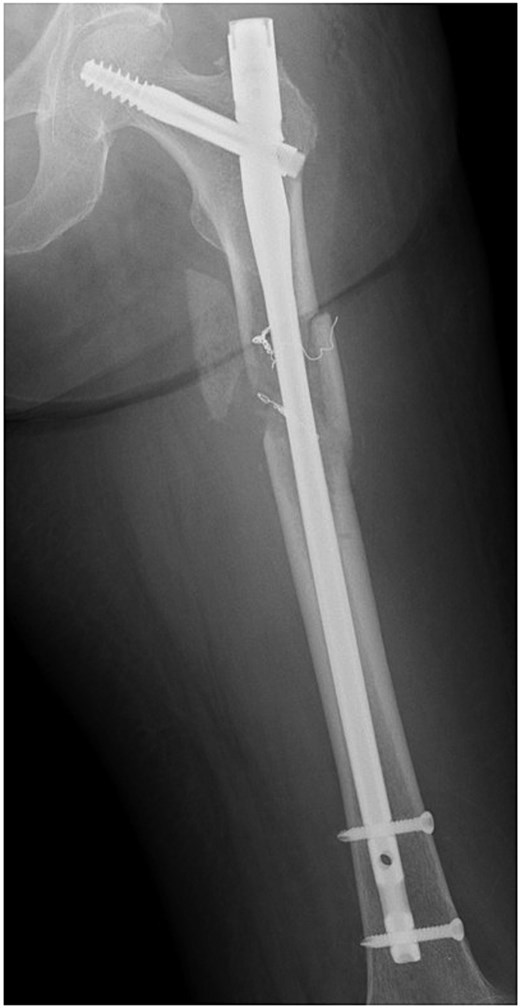

After interventional radiology, internal fixation with antegrade intramedullary nailing was performed using the blocking pin technique (Fig. 4). Tumour tissue from the fracture site was sent for pathology. The operative time was 63 min, and intraoperative blood loss (IBL) was 30 ml. She was allowed full weight-bearing depending on her condition.

The treatment strategy for pathological femoral fractures varies according to the patient's condition and prognosis [8]. This patient had a revised Katagiri score of 5, placing her in the intermediate-risk group with a predicted one-year survival rate of ~50% [9]. Although radical treatment for femoral bone metastasis could have been considered, palliative surgery was preferred due to poor general health. Closed reduction was performed using the Poller pin technique and internal fixation with an intramedullary nail. The blocking screw technique reportedly increases bone union rates while reducing IBL, complication rates, and hospital stay [10].